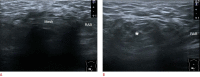

Inguinal hernia is the most prevalent type of abdominal wall hernia. Indirect inguinal hernia is twice as common as direct inguinal hernia. Computed tomography and magnetic resonance imaging can be used to evaluate inguinal hernia, but these modalities are greatly limited by their cost and availability. Ultrasonography has emerged as the most convenient imaging tool for diagnosing inguinal hernia due to its advantages, such as portability and absence of radiation. The present pictorial review presents an overview on the use of ultrasonography in the evaluation of inguinal hernia with a particular emphasis on the regional anatomy, relevant scanning tips, identification of subtypes, postoperative follow-up, and diagnosis of pathologies mimicking inguinal hernia.